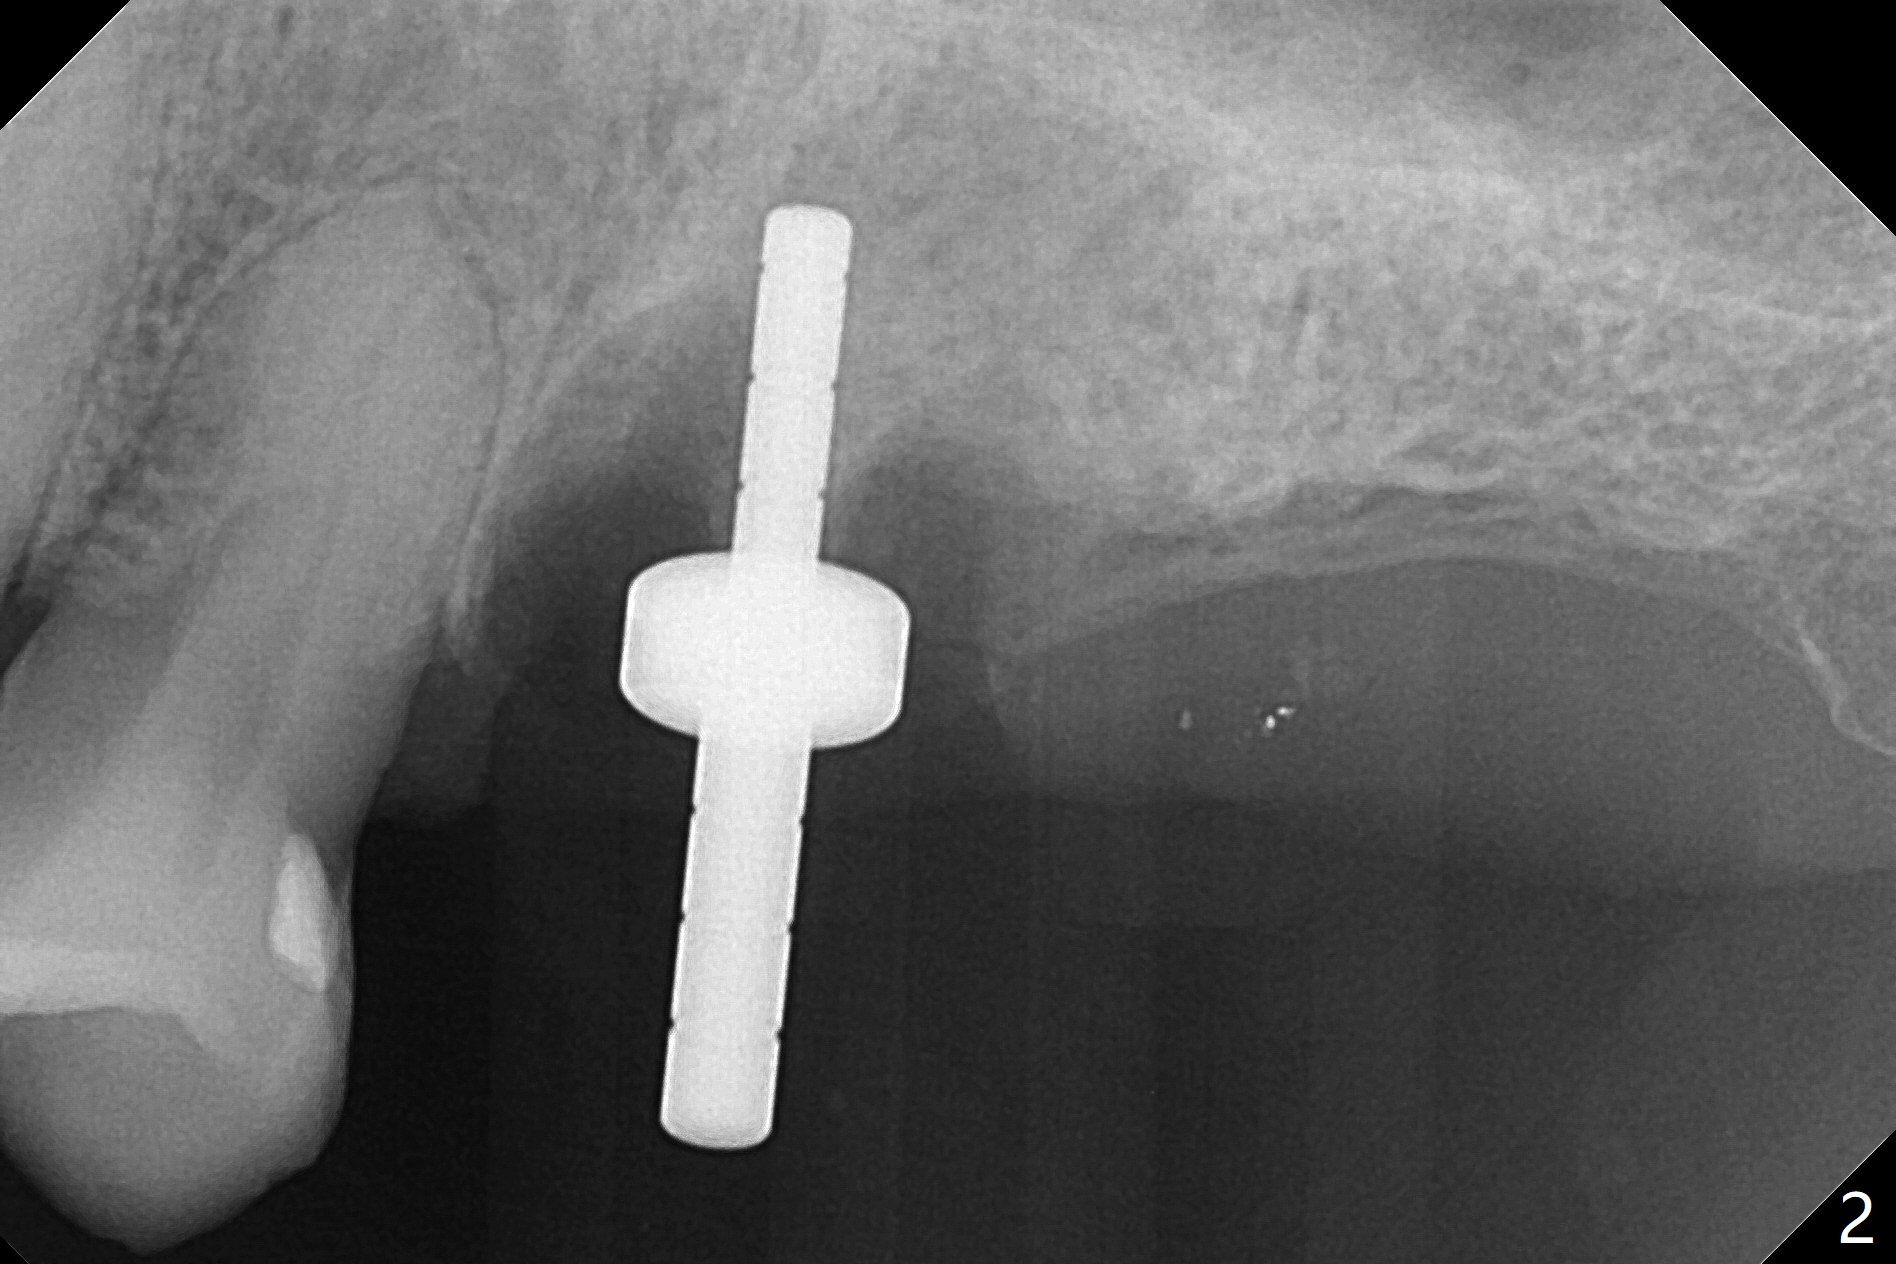

After extraction of the tooth #14 (Fig.1) and removal of granulation tissue associated with a distal fistula, a 1.6 mm drill is used to initiate osteotomy in the septum for 9 mm, followed by insertion of a 7 mm long parallel pin (Fig.2). The length of the subsequential osteotomy is 11 mm until 4.8 mm in diameter (overprep as will be shown below). The bone is hard so that sinus lift fails with 4.8 mm Magic Expander. Since a 5x9 mm dummy implant is placed with stability, a definitive implant with the same dimension is chosen with >50 Ncm (Fig.3,4). Prior to and after abutment placement, Vera graft is placed (*). The provisional perforates with loose abutment 3.5 months postop. A 6x4 mm healing abutment is placed. Osteointegration occurs 4 months postop (Fig.5,6).